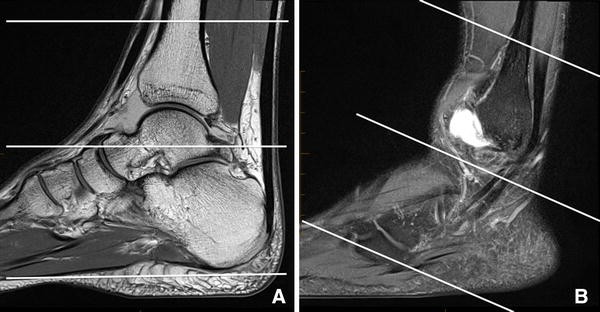

Radiology department of the scroll through the image stack for the ligamentous anatomy in the axial plane.

Describe the best imaging strategy utilizing mri to assess normal ankle anatomy. We think this is the most useful anatomy picture that you need. When everything works together, the ankle functions correctly. Webmd talks about the anatomy of the ankle magnetic resonance imaging (mri scan):